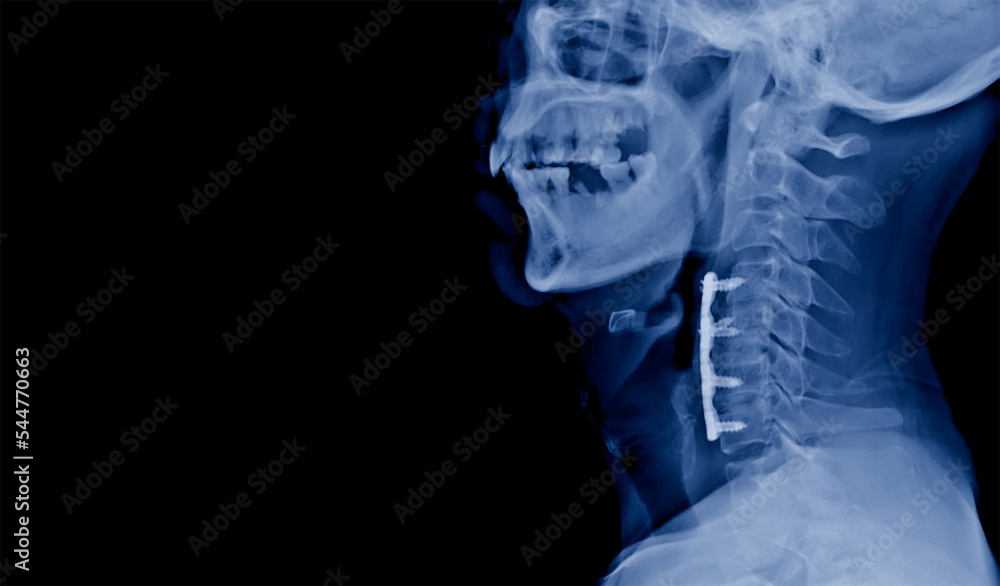

From stock.adobe.com

Lateral projection cervical spine xray showing anterior cervical Cord Compression Myelopathy this article will focus on atraumatic causes of spinal cord. The most common type is cervical spondylotic. myelopathy is an injury to the spinal cord due to severe compression that may result from trauma, congenital stenosis, degenerative disease or. cervical myelopathy is spinal cord compression in your cervical spine or neck. It is usually due to compression. Cord Compression Myelopathy.